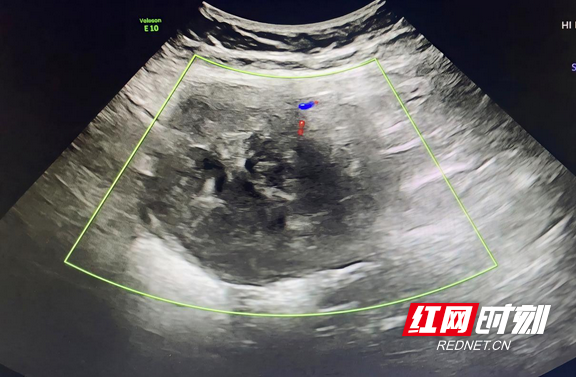

B超下肌瘤清晰可见(资料图片)。